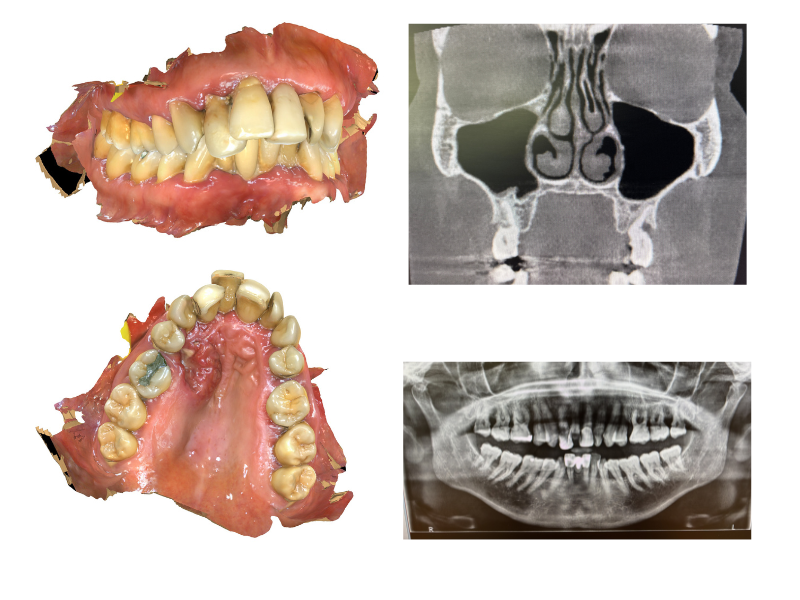

Before surgery, your clinical team will carry out detailed assessments to plan every aspect of your treatment. This includes CT scans and other imaging to map the tumour and surrounding anatomy, along with dental impressions to begin planning your new teeth.

The surgical and prosthodontic teams work together to determine the optimal positions for your implants, ensuring the best possible outcome for both tumour removal and dental restoration.

High-resolution CT imaging with dental protocol is essential for assessment of zygomatic bone stock and planning implant trajectories. Pre-operative dental impressions and jaw registration allow fabrication of surgical guides and enable prosthodontic planning to commence before surgery.

Two-team operating approach requires coordination between ablative surgeon, reconstructive surgeon, and maxillofacial prosthodontist. Virtual surgical planning may be employed for complex cases.

Assessment should include evaluation of remaining dentition, occlusal scheme, and potential implant sites on the non-defect side for cross-arch stabilisation.